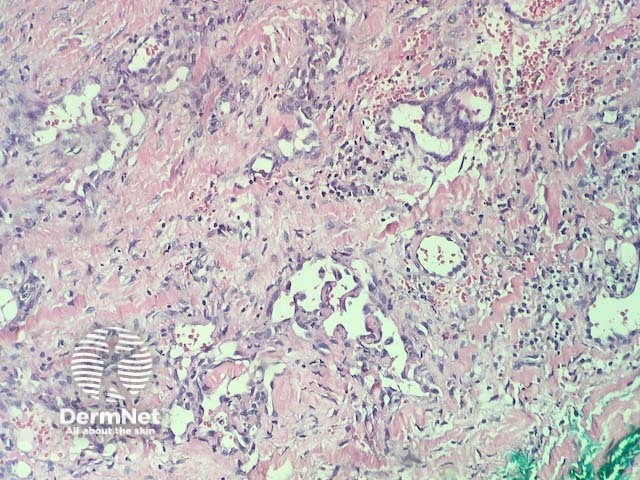

In verrucous haemangioma, the histopathology shows irregular papillomatosis, acanthosis and hyperkeratosis of the epidermis. The dermis shows multiple, thin-walled, dilated blood-filled spaces. Intravascular thrombosis with recanalisation and haemorrhage can be seen (figures 1–5).

Figure 3